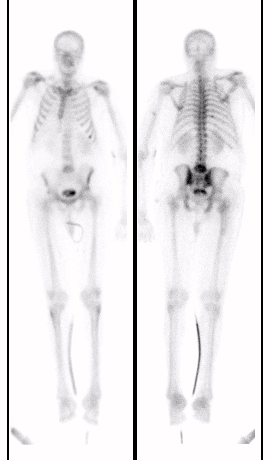

Metastatic prostate cancer on In-111 WBC imaging: The patient below was being evaluated for a fever of unknown origin. The WBC study revealed photopenic lesions involving the spine due to prostate metastases. |

|